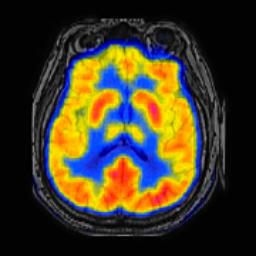

In image fusion, images obtained from different sensors are fused to generate a single image with enhanced information. In recent years, state-of-the-art methods have adopted Convolution Neural Networks (CNNs) to encode meaningful features for image fusion. Specifically, CNN-based methods perform image fusion by fusing local features. However, they do not consider long-range dependencies that are present in the image. Transformer-based models are designed to overcome this by modeling the long-range dependencies with the help of self-attention mechanism. This motivates us to propose a novel Image Fusion Transformer (IFT) where we develop a transformer-based multi-scale fusion strategy that attends to both local and long-range information (or global context). The proposed method follows a two-stage training approach. In the first stage, we train an auto-encoder to extract deep features at multiple scales. In the second stage, multi-scale features are fused using a Spatio-Transformer (ST) fusion strategy. The ST fusion blocks are comprised of a CNN and a transformer branch which capture local and long-range features, respectively. Extensive experiments on multiple benchmark datasets show that the proposed method performs better than many competitive fusion algorithms. Furthermore, we show the effectiveness of the proposed ST fusion strategy with an ablation analysis. The source code is available at: https://github.com/Vibashan/Image-Fusion-Transformer.